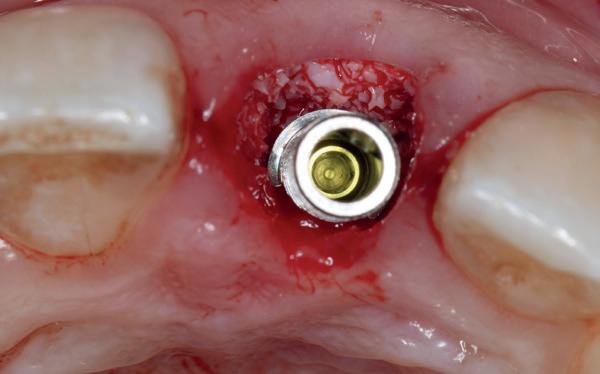

Afbeelding 1 en 2. Een immediate placement (afbeelding 1) is maar weinig invasief en zal weinig nalast geven. Bij een uitgebreide botopbouw (afbeelding 2) daarentegen is de wond veel groter en kan er meer nalast verwacht worden.

Bij uitgebreidere behandelingen zoals botbreedteen/of hoogteherstel is er vaak sprake van een groter chirurgisch gebied. De mucosa en het botvlies (periost) worden verder afgeschoven en vaak is het noodzakelijk om het rijkelijk doorbloede periost in te snijden (klieven) om de mucosa weer spanningsvrij te kunnen hechten na de ingreep. Dit heeft meer bloeding en zwelling tot gevolg, hetgeen weer meer druk geeft op het wondgebied. Ook de patiënt zelf is